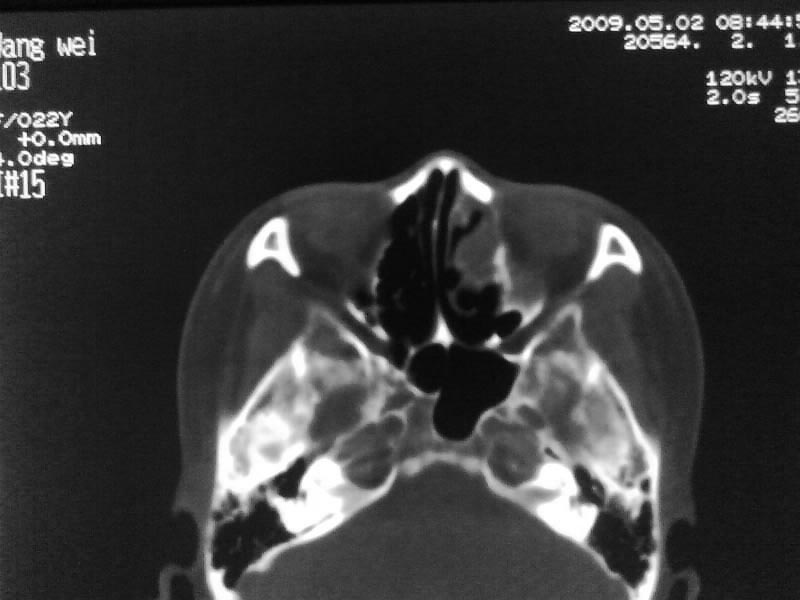

以下是引用zjzjr在2009-5-3 9:59:00的发言:[br]左侧鼻腔息肉、左侧筛窦、上颌窦炎症。双侧下鼻甲粘膜肥厚。

以下是引用随光逐影在2009-5-3 13:02:00的发言:[br]1)左侧鼻腔新生物(息肉可能)。2)左侧上颌窦及左侧筛窦炎症。3)双侧下鼻甲黏膜肥厚。